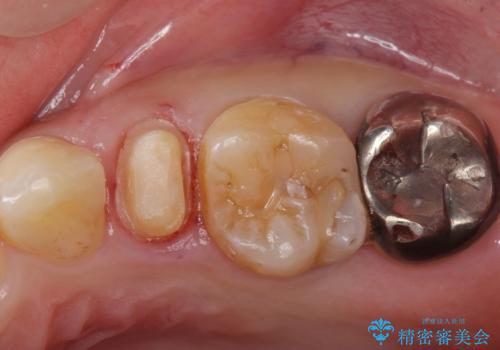

- 他院で被せた保険の白い被せ物(樹脂)をセラミックの被せ物に変えたいとの事で来院。

被せ物を外し、虫歯がないことを確認してセラミックの被せ物(ジルコニアクラウン)の治療を行いました。